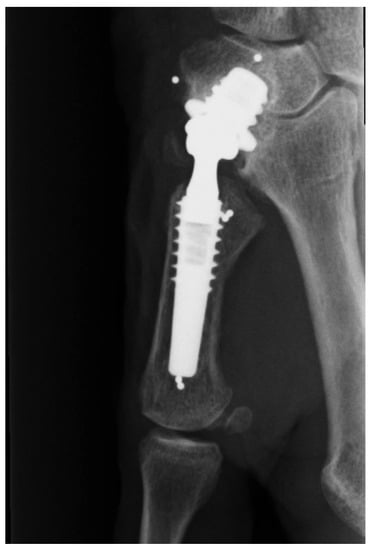

A 74-years old female was treated with a trapeziometacarpal MoM prosthesis due to osteoarthritis. The prosthesis used was a cementless Motec titanium Bonit® coated screw cup (Swemac AB, Linköbing, Sweden) with a chrome-cobalt insert (CoCrMo ISO 5832-12) for articulation. The cup comes in three sizes (7.0, 8.5, 10.0) and a size 8.5 was used. The cup was combined with a Motec titanium Bonit® coated metacarpal screw stem with a modular chrome-cobalt (CoCrMo ISO 5832-12) neck and head. The stem comes in four sizes and a size medium was used. Follow up at 29 months showed good function of the prosthesis with a DASH score of 3 (Disabilities of the Arm Shoulder and Hand score, range 0–100 where 0 represents no symptoms) compared to a pre-operative DASH score of 29. Conventional X-rays was found without radiolucent zones, bone resorption, change in position or any other signs of loosening (Figure 3). Blood samples showed elevated S-cobalt 25.4 nmol/L (normal < 10 nmol/L) and S-chrome 25.5 nmol/L (normal < 10 nmol/L). Metal ion levels were measured again three times with 3 months interval, and were found to be continuously at the same level. The patient had some skin rash problems, and insisted on having the prosthesis removed due to the elevated metal serum levels. During surgery the prosthesis showed clear signs of wear at the dorso-radial rim and the preprosthetic tissue was seen to be slightly discolored (Figure 4). However, there were no signs of pseudo tumor formation or discoloration of the bone, and the implant was found well fixated to the bone.

Figure 3.

Radiograph without signs of implant failure after 29 months.